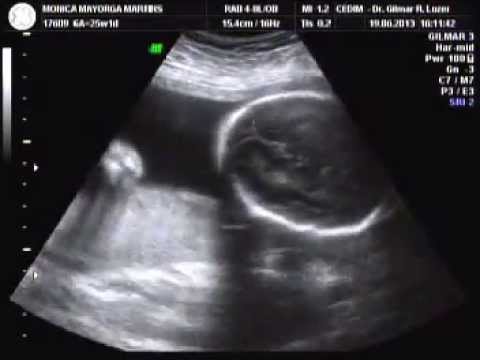

Olha filhão, quantas emoções estamos vivendo, hoje posto no nosso blog o seu ultrassom com 25 semanas, é incrível você abrindo a boquinha, sua linguinha indo e voltando, meu filho te ver nos faz muito feliz, não dá para descrever o amor que sentimos por ti!!! Vc é uma benção de DEUS em nossas vidas!!!